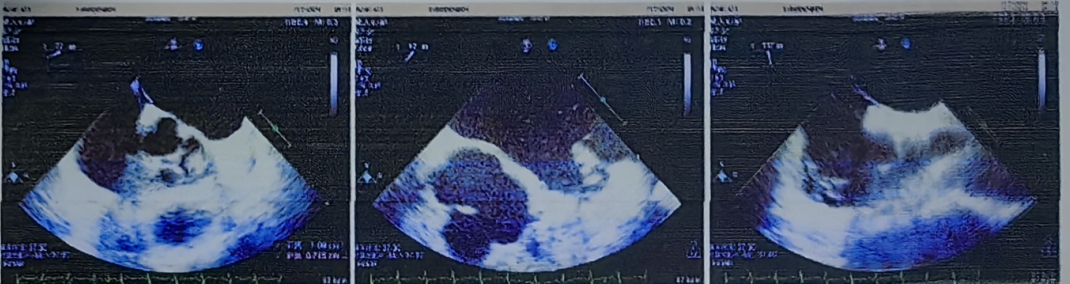

超声结果提示。

封堵器成型良好。

在对林先生进行局部麻醉后,医生通过穿刺右股静脉,仅耗时十分钟便将封堵器送达未闭的卵圆孔处进行封堵。术后超声提示,封堵器位置良好,形态固定,房水平未见分流,达到预定封堵效果,患者头痛症状消失。